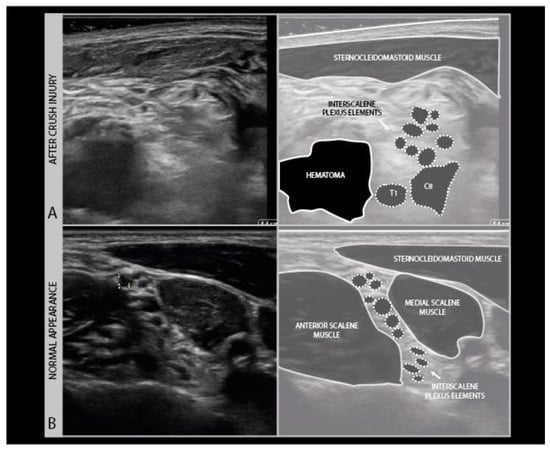

To assess the nerves for abnormality, it is strongly advised to scan the nerve all the way along its accessible length, looking for sudden changes in size or appearance. When an abnormality is found, it is advisable to also twist the probe 90° around and make a longitudinal image of the lesion site. When measuring neuroma sizes, placing several diameter markers proximal, at and caudal to the lesion site may be helpful (Figure 3).

Figure 3.

Image examples of transverse cross-sectional area (CSA) (A) versus longitudinal diameter measurement (B). A: distal ulnar neuroma; B: distal median nerve neuroma (adult male with a crush injury of the distal forearm). ULN = ulnar nerve.